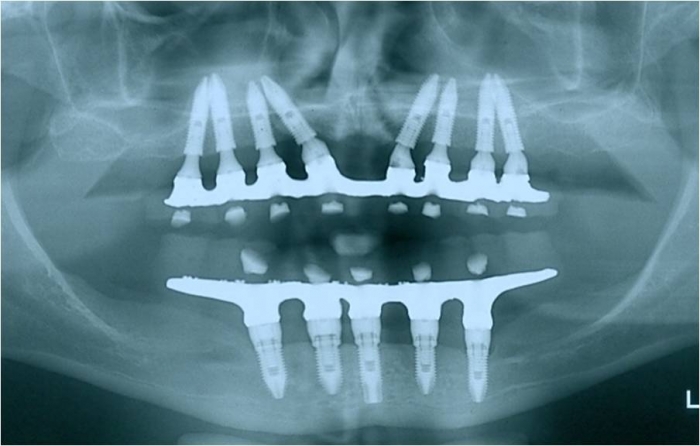

Rx dos implantes Cone Morse superiores

Raio X final